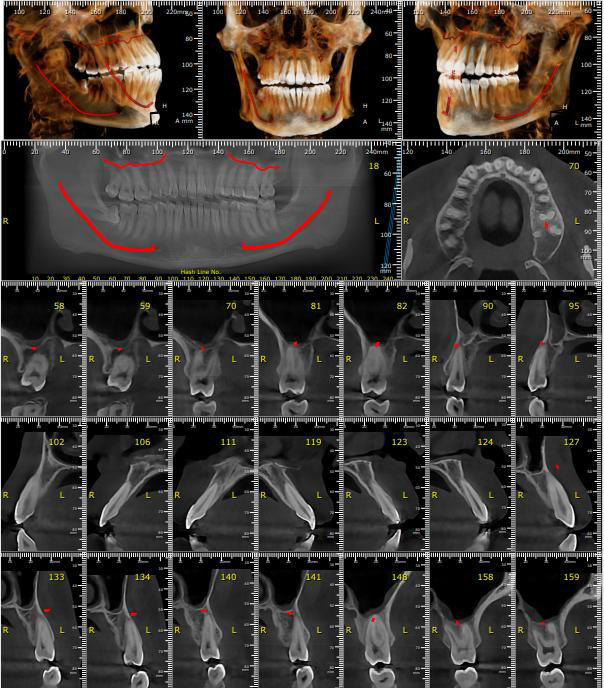

On examination, we found:

- Deep bite and restricted jaw movement

- Severe muscle tenderness (masseter, temporalis, pterygoid)

- Jaw deviation with function

- MRI confirmed his TMJ dysfunction